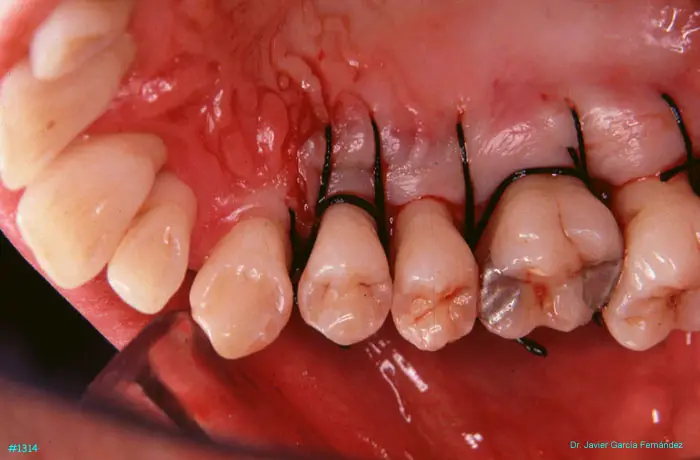

Atlas of Surgical Techniques in Periodontics. Chapter III. Atlas de Técnicas Quirúrgicas en Periodoncia